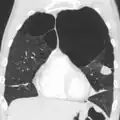

Outros exames

A realização de uma radiografia ao tórax e de um hemograma permitem excluir outras condições no momento do diagnóstico.[69] Os sinais característicos da DPOC observáveis em radiografia são pulmões sobre-expandidos, diafragma achatado e espaço retroesternal aumentado. Ao mesmo tempo, a radiografia permite excluir outras doenças pulmonares, como pneumonia, edema pulmonar ou pneumotórax.[70] Uma tomografia axial computorizada ao tórax permite mostrar a distribuição do enfisema pelos pulmões e pode ajudar a excluir outras doenças pulmonares.[18] No entanto, a não ser nos casos em que se planeie a realização de uma cirurgia, esta distribuição raramente influencia o tratamento.[18] Pode ainda ser realizada uma gasometria arterial para determinar a necessidade de oxigénio suplementar. Este exame é recomendado em pessoas com VEF1 inferior a 35% do previsto, com saturação periférica de oxigénio inferior a 92% e pessoas com sintomas de insuficiência cardíaca congestiva.[17] Em regiões do mundo onde é comum a deficiência de alfa-1 antitripsina, as pessoas com DPOC devem considerar a realização deste exame, sobretudo aquelas com idade inferior a 45 anos e em que o enfisema afeta a parte inferior dos pulmões.[17]

Caso grave de enfisema bolhoso

Caso grave de enfisema bolhoso -

TAC axial do pulmão de uma pessoa em estado terminal de enfisema bolhoso.

TAC axial do pulmão de uma pessoa em estado terminal de enfisema bolhoso. -